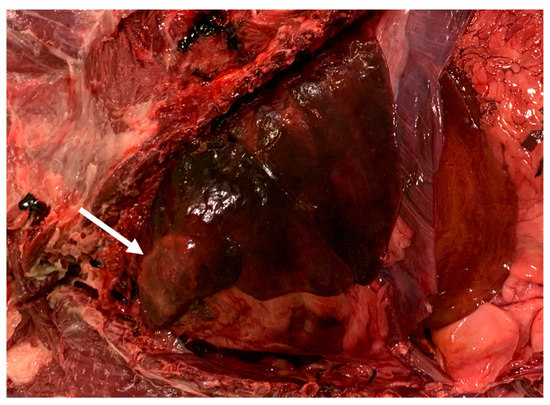

2.4. Necroscopic Examination and Histopathology